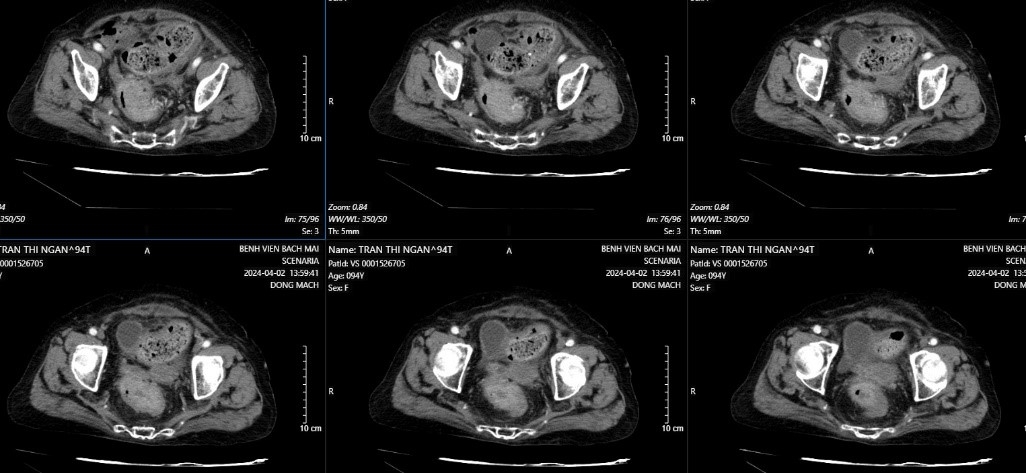

Cắt lớp vi tính ổ bụng: Dày thành đại lên không đều, chỗ dày nhất 14mm, trên đoạn dài 48mm, ngấm thuốc mạnh, thâm nhiễm mỡ xung quanh

Hình 1: Dày thành không đều đại tràng phải

Cùng tuổi “bách niên” giống cụ H, ngày 1/4/2024, cụ bà Phạm Thị L, 94 tuổi cũng vào viện vì đại tiện khó kèm nhày máu. Cụ L cũng mắc chứng cao huyết áp kèm sốt cao 39 độ. Chụp cắt lớp: Tổn thương đông đặc thùy trên và giữa phổi phải. Dày thành không đều trực tràng cao trên đoạn 9cm, chỗ dày nhất 39mm, xâm lấn ra lớp ngoài thanh mạc, chưa xâm lấn đến mạc treo trực tràng, tạo khối lồi vào lòng trực tràng gây hẹp. Kết quả Nội soi: Khối sùi loét nham nhở chiếm gần hết lòng chu vi cách rìa hậu môn 8cm, máy soi không qua được.

Hình 4. CLVT hình ảnh u trực tràng bệnh nhân L.